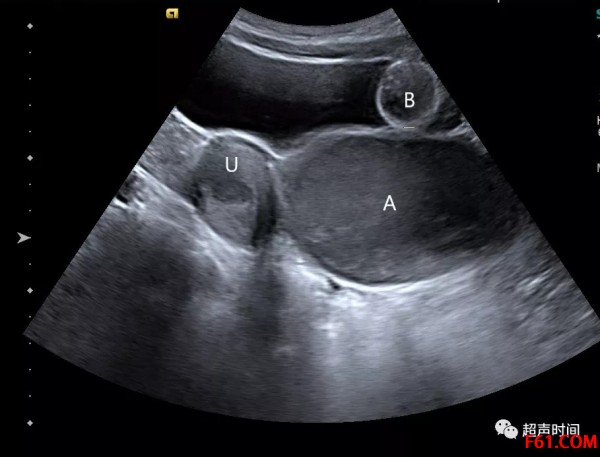

处女膜闭锁超声图

图 1 示子宫(U)宫腔分离,阴道内呈囊性回声(A)。B:导尿管球囊

超声所见:子宫大小、形态正常,肌层回声均匀,宫腔分离约 0.9 cm。阴道壁薄而平滑,其内探及范围约 9.4×5.7 cm 囊性回声区(图 1 和图 2),内可见密集点状回声,未见明显血流信号。盆腔内未见明显液性暗区及其他异常回声。

超声提示:宫腔及阴道内积血,考虑处女膜闭锁所致。